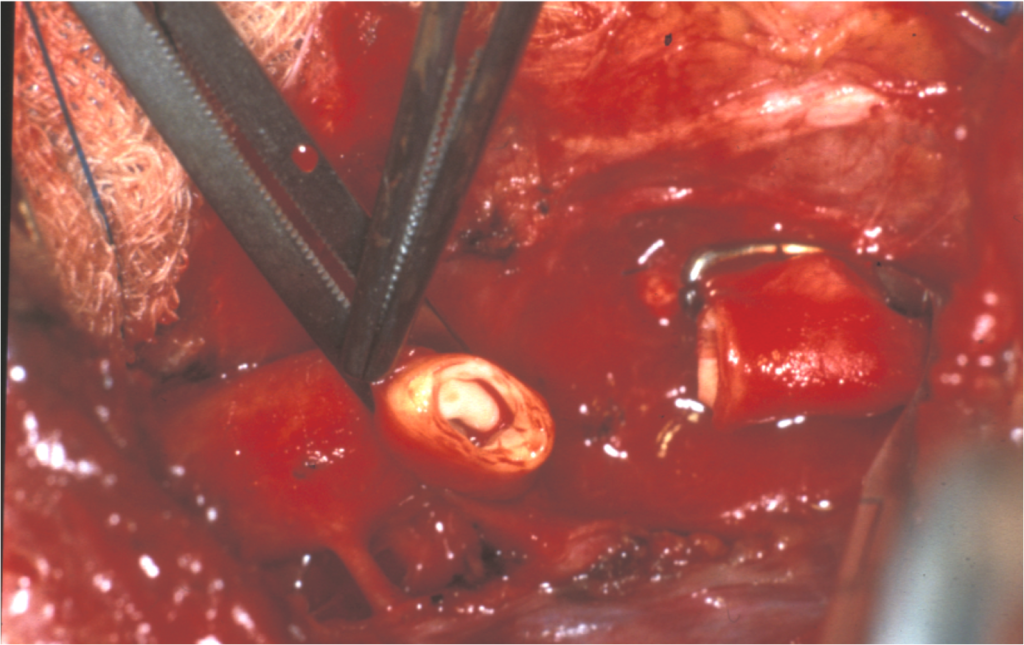

Coarctation of the Aorta

Coarctation of the aorta results in an abnormal narrowed portion of the aorta.

Coarctation of the aorta is separated into juvenile and adult versions.

Adult version of coarctation of the aorta

A patent ductus arteriosus (PDA) is not connected to adult form of coartctation of the aorta.

After (distal to) the aortic arch is where the coarctation is typically located in adults.

Coarctation of the aorta in adults typically presents with:

- Hypertension in the upper extremities

- Hypotension with weak pulses in the lower limbs

Radiology of coarctation of the aorta classically shows “notched ribs” on an x-ray due to collateral vessels.

Coarctation of the aorta is linked with the bicuspid aortic valve.